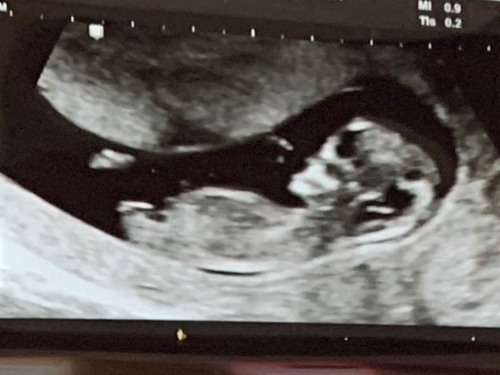

Iemand al een idee misschien nog te vroeg maar wie weet ♡

Iemand een idee? Denk wat vroeg, maar je weet t nooit 😋 11+2

Enig idee wat het geslacht is? :) 10 weken + 6 dagen!